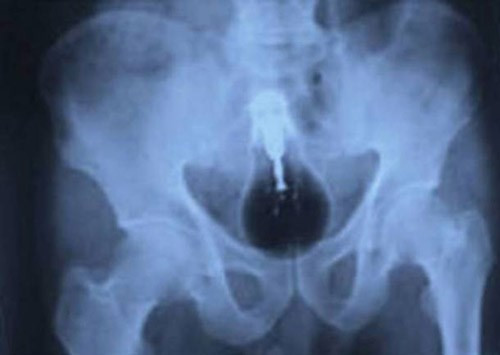

Người phụ nữ dấu tên kể lại, cô dùng chiếc lược mảnh để chọc viên thuốc đang mắc ở cổ họng nhưng không may nó tuột xuống và cô không tài nào gỡ ra được. Chiếc lược chèn ngay nơi cổ họng rồi lại trôi xuống cuống họng làm cô ngất đi và được đưa vào cấp cứu tại bệnh viện đại học Akdeniz.

Tại đây, các bác sỹ đã phẫu thuật gần một giờ đồng hồ để lấy dị vật trong cơ thể này ra. Nếu như chậm vài phút nữa là chiếc lược 20cm sẽ làm nghẹt đường thở của bệnh nhân gây tử vong.